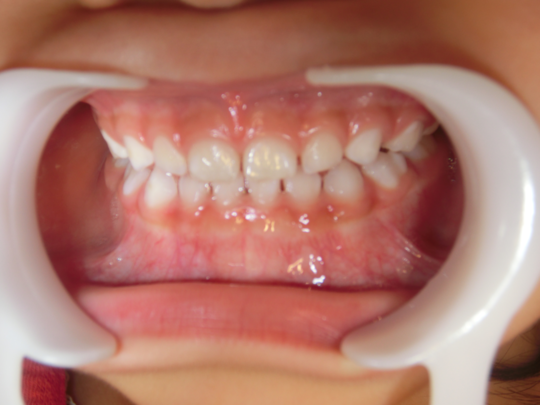

治療後

治療の副作用(リスク)歯の動き方には個人差があり、予想された治療期間が延長する可能性があります。。床矯正の使用状況、矯正歯科治療には患者さんの協力が必要であり、それらが治療結果や治療期間に影響します。2次矯正が必要になる場合もあります。